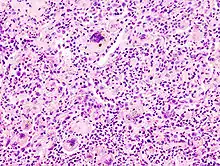

Reed-Sternberg cell

Reed-Sternberg cells are generally thought to originate from B-lymphocytes.[14] They are hard to study due to their rarity, and there are other theories about the origins of these cells. Some less popular theories speculate that they may arise from the fusion between reticulum cells, lymphocytes, and virus-infected cells.[15]

Similar to other MGCs, Reed-Sternberg cells are large and are either multinucleated or have a bilobed nucleus. Their nuclei are irregularly shaped, contain clear chromatin, and possess an eosinophilic nucleolus.